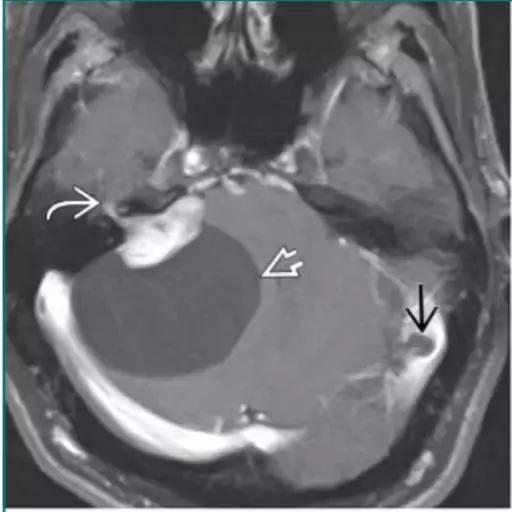

脑包虫囊肿